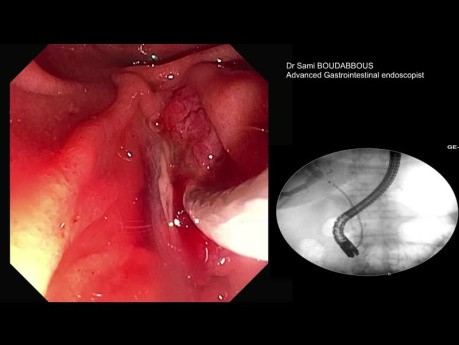

Stent Métallique Auto-Expansible pour Cancer...

Femme de 78 ans, traitée il y a 6 semaines pour une obstruction biliaire liée à un cancer avancé de la tête du pancréas. Elle avait une endoprothèse biliaire en plastique de 10 fr x 7 cm. Elle présentait...

CPRE pour Calculs du Cholédoque de Grande Taille...

Cas vidéo endoscopique : homme de 55 ans atteint d'angiocholite aiguë.- sous traitement antidiabétique oral depuis 20 ans.- cholangite aiguë liée à un calcul de CBD de 14 x 25 mm. Cholécystectomie réalisée...